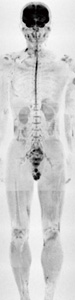

頭部では圧倒的な画質を提供できる3.0T装置も,近年では腹部にフォーカスした最適化が進み,最近では1.5T装置と同等以上の画像を提供できるようになってきた。内蔵Bodyコイルを用いて撮像される全身DWIについても,1.5Tでスキャンされる画像と比較してまったく遜色がなく,SNRの点で言えばむしろ1.5Tよりも良好な結果を得ている(図8)。これは,高い静磁場均一性や高性能な内蔵Bodyコイルがあってこその結果である。

図8 3.0T装置による全身DWI

内蔵Bodyコイルにて撮像。(画像ご提供:長野市民病院様)